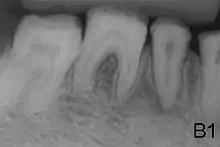

AI can be classified according to their clinical appearances:[18]

- Type 1 - Hypoplastic

- Enamel of abnormal thickness due to malfunction in enamel matrix formation. Enamel is very thin but hard & translucent, and may have random pits & grooves. Condition is of autosomal dominant, autosomal recessive, or x-linked pattern. Enamel differs in appearance from dentine radiographically as normal functional enamel.[19]

- Enamel defect due to malfunction of enamel calcification, therefore enamel is of normal thickness but is extremely brittle, with an opaque/chalky presentation. Teeth are prone to staining and rapid wear, exposing dentine. Condition is of autosomal dominant and autosomal recessive pattern. Enamel appears less radioopaque compared to dentine on radiographs.